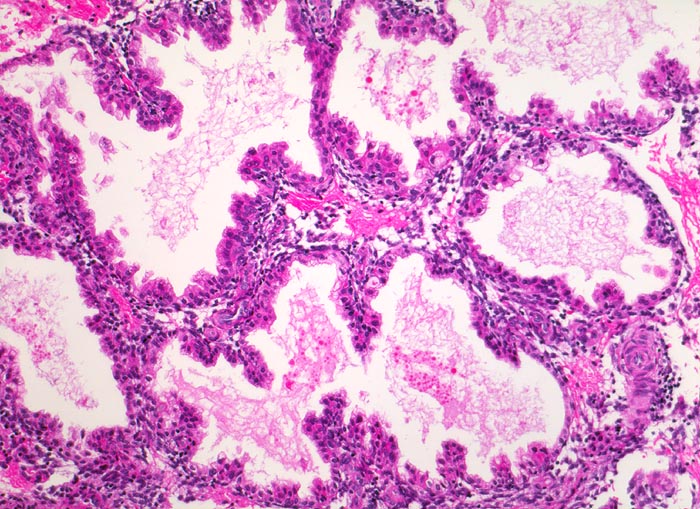

Chromosomenaberrationen verursachen nicht nur beim Feten, sondern auch an der Chorionzotte morphologisch fassbare Entwicklungsstörungen: mangelnde Verzweigungen, wandernde Trophoblastzellen im Stroma, mangelhafte Vaskularisation, hydropische Alteration des Stromas und herdförmige Atrophie oder auch Hyperplasie des Trophoblasten sind typische Befunde bei einer Chromosomenaberration. Aborte mit Triploidie zeigen in der grossen Mehrzahl das Bild einer Partialmole. Eine Tetraploidie kann das Bild einer Windmole (=Windei), einer Embryonalmole oder seltener einer Partialmole verursachen. Autosomale Trisomien können ebenfalls als Windmole oder als Embryonalmole imponieren. In nur etwa 25% aller Spontanaborte sind bei der pathomorphologischen Untersuchung ein Embryo, Embryofragmente oder ein Nabelschnuranteil nachweisbar. Die morphologische Untersuchung des Abortmaterials stellt eine wichtige Ergänzung zu den klinischen Befunden dar.

• Vergrösserte Plazentarzotten mit hydropischem Zottenstroma.

• Vereinzelt Zytotrophoblasteinschlüsse im Stroma.

• Vorwiegend einschichtiges Zytotrophoblastepithel ohne Atypien und mehrkerniger Synzytiotrophoblast. Physiologische polare Trophoblastproliferate.